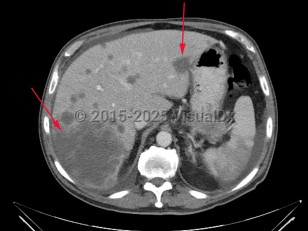

Liver cancer

Synopsis

Many malignancies can metastasize to the liver. Frequently, patients with uveal melanoma may have liver metastases. In rare circumstances, lymphomas can present with primary manifestation in the liver.